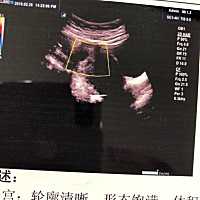

羊水多。29周6天的单子